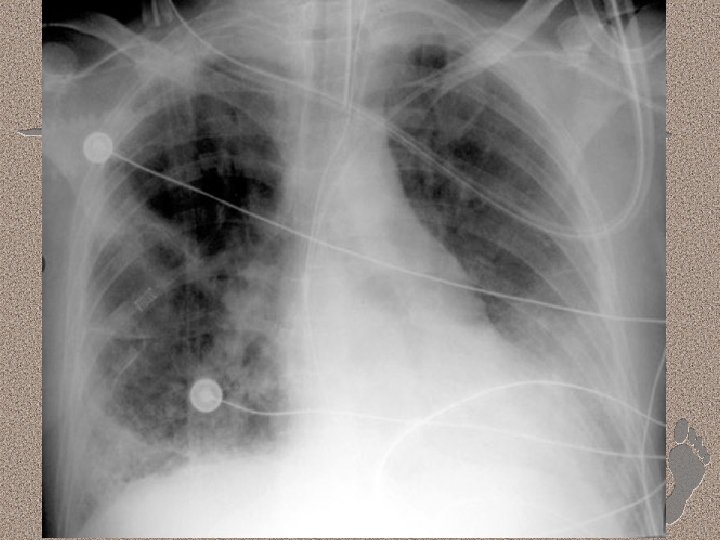

Pemeriksaan Penunjang • Laboratorium • AGD : alkalosis respiratorik pada fase awal, dan berganti menjadi asidosis respiratorik pada fase lanjut • Leukositosis (sepsis), anemia, trombositopenia (SIRS), peningkatan kadar amilase (pankreatitis) • Gangguan fungsi ginjal dan hati. • Pencitraan • • Foto dada : gambaran radioopak difus CT-Scan : pola heterogen, predominasi infiltrat pada dorsal paru (supine)